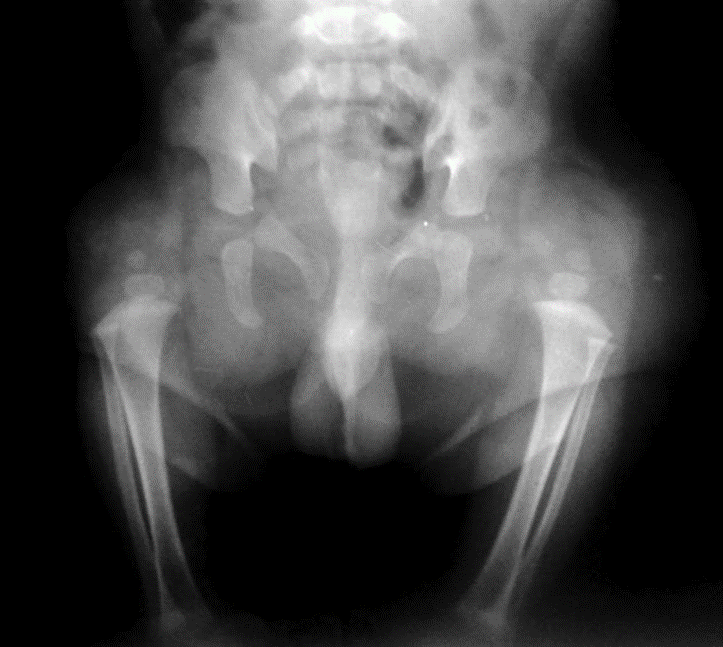

Proximal focal femoral deficiency (PFFD) is radiologically classified into types using the Aitken classification.

Bilateral Proximal focal femoral deficiency (class B on right side and class C on left side).

Congenital marked hypoplasia of both femurs consistent with bilateral proximal focal femoral deficiency. femoral head and almost all the femur are absent bilaterally, associated with absent acetabula. This is consistent with class D deformity.